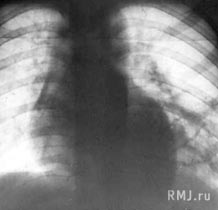

Рентгеновские снимки при врожденной эмфиземе легкого

Раздел: Визуальные уроки